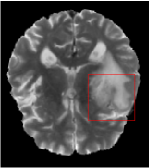

Qualitative comparison between conventional and Meta-learning methods are shown in Figure 1 and 3, which display the reconstructed MR images of the same slice for T1 and T2 respectively, we label the zoomed-in details of HGG in the red boxes. We observe the evidence that conventional learning is more blurry and lost sharp edges, especially in lower CS ratios. From the point-wise error map, we find meta-learning has the ability to reduce noises especially in some detailed and complicated regions comparing to conventional learning.

In this section, we test the generalizability of the proposed model that tests on unseen tasks. We fix the well-trained task-invariant parameter and only train for sampling ratios 15%, 25% and 35% with radio masks and sampling ratios 10%, 20%, 30% and 40% with Cartesian masks. In this experiment, we only used 100 training data for each CS ratio and apply a total of 50 epochs. The averaged evaluation values and standard deviations are listed in Table 5.4 and 5.4 for reconstructed T1 and T2 brain images respectively that proceed with radio masks, and Table 5.4 shows the qualitative performance for reconstructed T2 brain image that applied random Cartesian sampling masks. In T1 image reconstruction results, meta-learning improved 1.6921 dB in PSNR for 15% CS ratio, 1.6608 dB for 25% CS ratio, and 0.5764 dB for 35% comparing to the conventional method, which in the tendency that the level of reconstruction quality for lower CS ratios improved more than higher CS ratios. A similar trend happens in T2 reconstruction results with different sampling masks. The qualitative comparisons are illustrated in Figure 2, 4 and 5 for T1 and T2 images tested in skewed CS ratios in radio masks, and T2 images tested in Cartesian masks with regular CS ratios respectively. In the experiments that conducted with radio masks, meta-learning is superior to conventional learning especially at CS ratio 15%, one can observe that the detailed region in red boxes keeps edges and is more close to the true image, while conventional method reconstructions are hazier and lost details in some complicated tissue. The point-wise error map also indicates that Meta-learning has the ability to suppress noises.